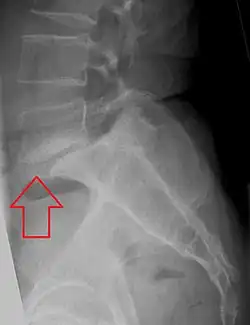

![]() | |

| X-ray of the lateral lumbar spine with a grade III anterolisthesis at the L5-S1 level | |

Spondylolisthesis refers to a condition in which one spinal vertebra slips out of place compared to another.[1] While some medical dictionaries define spondylolisthesis specifically as the forward or anterior displacement of a vertebra over the vertebra inferior to it (or the sacrum),[2][3] it is often defined in medical textbooks as displacement in any direction.[4][5]

Spondylolisthesis is graded based upon the degree of slippage of one vertebral body relative to the subsequent adjacent vertebral body.[6] Spondylolisthesis is classified as one of the six major etiologies: degenerative, traumatic, dysplastic, isthmic, pathologic, or post-surgical.[7] Spondylolisthesis most commonly occurs in the lumbar spine, primarily at the L5-S1 level, with the L5 vertebral body anteriorly translating over the S1 vertebral body.[7]